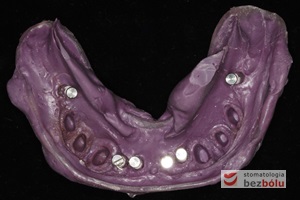

Model gipsowy żuchwy z szablonem chirurgicznym - metalowe tuleje wyznaczają miejsce wprowadzenia wszczepów - widoczne w obrazie RTG

Model gipsowy żuchwy z szablonem chirurgicznym – metalowe tuleje wyznaczają miejsce wprowadzenia wszczepów – widoczne w obrazie RTG